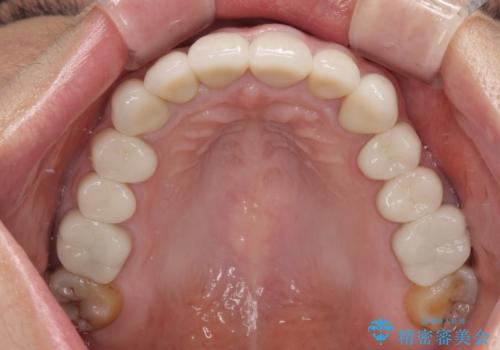

上顎前歯は樹脂による変色を覆い隠す処置が行われていましたが、汚れが溜まりやすく厚みも増している状態でした。

上顎前歯は樹脂を外し、下顎前歯の隙間はそれぞれの歯を大きくするように補綴治療を行うことで隙間を埋めることとしました。

口を開けたときに見える範囲をオールセラミッククラウンとし、とても自然な口元に仕上げることができました。